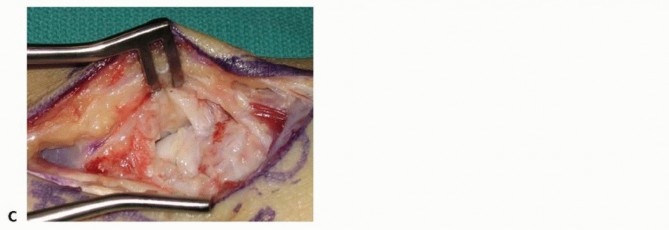

The harvested graft is meticulously shaped on the back table using a rongeur or a fine burr to perfectly match the dimensions of the scaphoid defect. The graft is then press-fit into the volar void with the cortical surface facing volarly to act as a structural buttress, and the cancellous portion facing the medullary canal to promote osteogenesis. The joysticks are relaxed, allowing the native ligamentous tension to compress the scaphoid fragments against the newly inserted wedge graft, locking it securely in place.

Rigid internal fixation is then achieved. A 0.035-inch guidewire for the cannulated headless compression screw is introduced from the distal scaphoid tubercle, directed proximally, dorsally, and ulnarly, aiming for the absolute central axis of the proximal pole. The trajectory is verified in multiple planes using intraoperative fluoroscopy. Achieving a central position in the proximal pole is statistically correlated with higher union rates and superior biomechanical pull-out strength.